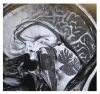

Idiopathic normal pressure hydrocephalus (iNPH) is the most common cause of hydrocephalus in adults. The diagnosis may be challenging, requiring collaborative efforts between different specialists. According to the International Society for Hydrocephalus and Cerebrospinal Fluid Disorders, iNPH should be considered in the differential of any unexplained gait failure with insidious onset. Recognizing iNPH can be even more difficult in the presence of comorbid neurologic disorders. Among these, idiopathic Parkinson's disease (PD) is one of the major neurologic causes of gait dysfunction in the elderly. Both conditions have their peak prevalence between the 6th and the 7th decade. Importantly, postural instability and gait dysfunction are core clinical features in both iNPH and PD. Therefore, diagnosing iNPH where diagnostic criteria of PD have been met represents an additional clinical challenge. Here, we report a patient with parkinsonism initially consistent with PD who subsequently displayed rapidly progressive postural instability and gait dysfunction leading to the diagnosis of concomitant iNPH. In the following sections, we will review the clinical features of iNPH, as well as the overlapping and discriminating features when degenerative parkinsonism is in the differential diagnosis. Understanding and recognizing the potential for concomitant disease are critical when treating both conditions.